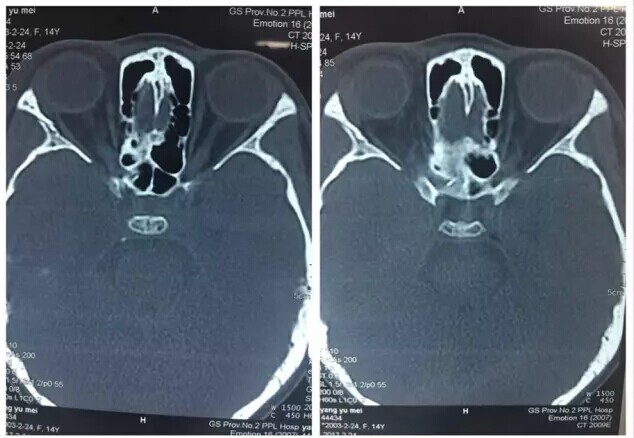

甘肃省二院眼科开展经眼眶视神经减压术使许多外伤失明的患者重见光明------2017-04-28 发布时间:2017-04-28 来源: 作者: